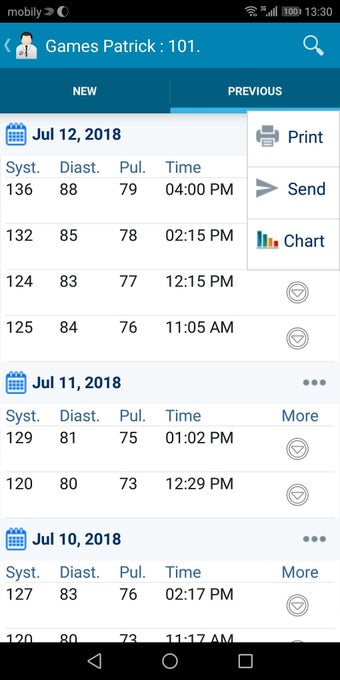

In addition, the app has a blood pressure module that measures systolic, diastolic, and pulse, and allows users to export blood pressure reports to either PDF or graphs. The app also has a blood glucose (sugar) module that records blood sugar values and allows users to export blood glucose reports to either PDF or graphs. Users can also send blood pressure and blood sugar reports to their doctor. The app is compatible with multiple screens, including phones and tablets, and works on Chromebook systems. Overall, the Android Medical Records App is a great tool for patients and physicians alike for managing patient information and medical records.